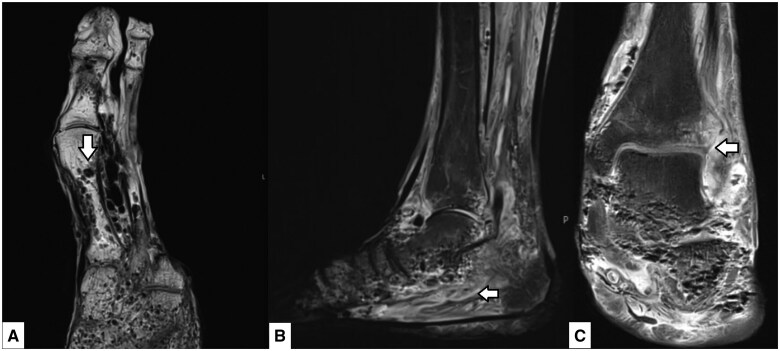

肺气肿性骨髓炎(EO)是一种罕见但严重的骨髓炎,其特征是骨内形成气体。本病例报告强调了一个截肢足的特别严重的EO病例,不同模式的关键影像学发现强调了诊断的挑战和早期发现的重要性。68岁男性,糖尿病控制不佳病史,因溃疡未愈合而截肢左三至第五趾,以感染图片和血糖控制不佳来到急诊科。经临床评估,发现感染病灶位于左脚,随后通过x线平片、MRI和CT进行评估。该病例强调了每种模式在这种复杂表现中的作用,包括平片上的骨小梁改变,MRI上的软组织改变和CT上的骨内肺病的确认。本病例强调了EO的主要影像学特征,并强调了使用CT和MRI及时指导手术和医疗管理的必要性。本报告补充了有限的EO文献,并提出了一个有用的缩写“LEAP”来描述怀疑EO时的关键特征-缺乏皮质破坏,骨外软组织气体,相关合并症(糖尿病,恶性肿瘤等)和浮石征。

Emphysematous osteomyelitis (EO) is an uncommon but severe form of osteomyelitis that is characterized by gas formation within the bone. This case report highlights a case of particularly severe EO in an amputated foot, with key imaging findings across modalities emphasizing the diagnostic challenges and the importance of early detection. A 68-year-old male with a history of poorly controlled diabetes and a previous left third to fifth toe amputation for a non-healing ulcer presented to the emergency department with an infective picture and poorly controlled blood glucose levels. After clinical assessment, a focus of infection was found in the left foot and was subsequently assessed with plain radiography, MRI, and CT. The case highlighted the utility of each modality in such a complex presentation, including trabecular bony changes on the plain radiograph, soft tissue changes on MRI and confirmation of intraosseous pneumatosis on CT. This case highlights key imaging features of EO and underscores the need to use CT and MRI to guide timely surgical and medical management. This report adds to the limited literature on EO and presents a useful acronym of "LEAP" to describe key features when suspecting EO - lack of cortical destruction, extra-osseous soft tissue gas, associated comorbidities (diabetes, malignancy, etc), and pumice stone sign.